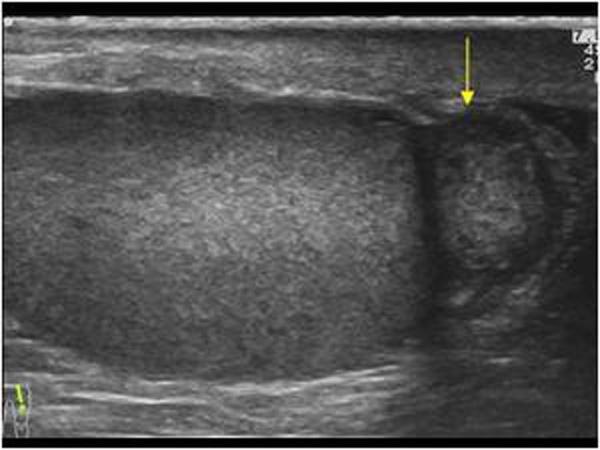

most common germ cell tumor

white male smoker

infertility

Seminoma

25 - 35 year olds

most aggressive testicular cancer

elevated beta-hcg

elevated AFp

Embryonal Cell carcinoma

common in infants

25 - 35 year olds

Testicular Teratoma

most common testicular tumor in infants and young children

elevated afp

Yolk sac tumors

20 - 30 year old

elevated beta-Hcg

Choriocarcinoma